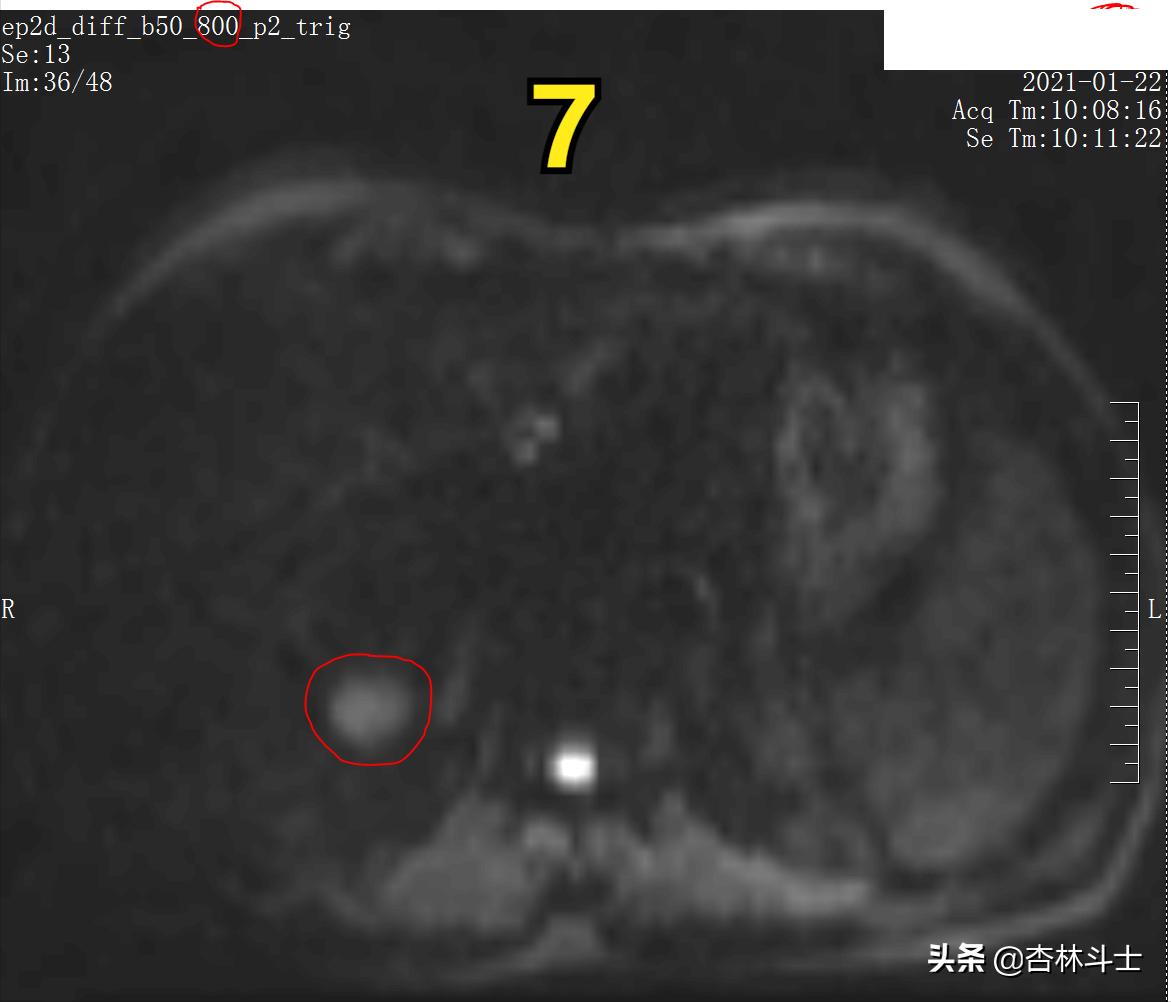

图7 DWI b800

图7 为高b值弥散加权图像(DWI),病灶呈高信号。此序列目的为了解人体内水分子“布朗运动”情况,肿瘤病灶内细胞密度高,肿瘤细胞代谢旺盛,细胞内细胞器多,细胞核大,种种原因,限制了肿瘤组织内的水分子运动,使得肿瘤病灶在DWI上呈高信号。

b值越高,越凸显身体内水分子弥散受限程度。

图6、7为弥散加权像,新发病灶在弥散加权上弥散受限,呈高信号。